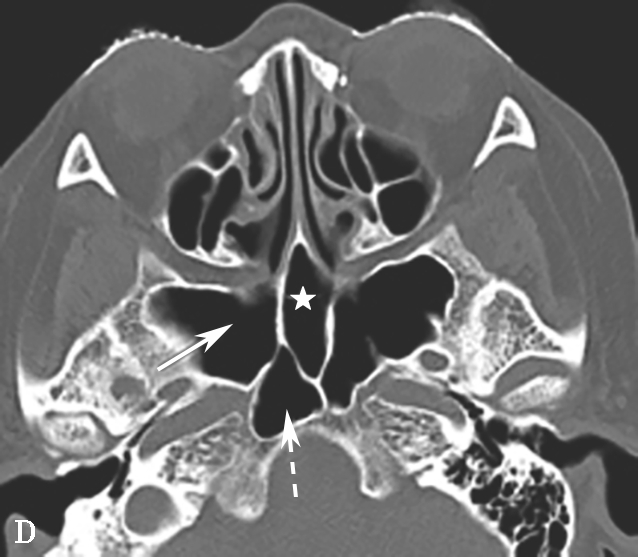

蝶窦气化可扩展到前窗突、翼突,分别称为前窗突气化、翼突气化,有时后床突、蝶骨小翼或鞍背也可气化,这些变异增加了损伤周围的重要结构(比如视神经管、翼管、圆孔等)的机会,术前应仔细地观察。

颈内动脉管突入蝶窦内,有时颈内动脉管壁可缺如,在行蝶窦手术时应注意此种情况,避免损伤造成严重的并发症,而这些变异只能根据CT来确定。

蝶窦常见解剖变异包括:①有分隔的蝶窦,可为纤维或骨性分隔分成几个不对称的部分,此变异容易导致蝶窦手术引流不完全而残留病变;②介甲型蝶窦,窦腔略有气化,发育很小,窦腔后缘与鞍结节垂直线之间尚有10mm厚骨质;③鞍前型蝶窦,蝶窦发育较小,窦腔后缘与鞍结节垂直线相齐,恰好位于蝶鞍之前,蝶鞍底大部分为松质骨;④半鞍型蝶窦,发育尚好,后上缘占鞍底前半部;⑤全鞍型蝶窦,发育良好,自鞍结节至鞍背连线的全鞍底与蝶窦只一层薄骨板;⑥枕鞍型蝶窦,与全鞍型相似,但发育更大,后缘超过鞍背垂线,蝶窦侵入枕骨使斜坡骨板更薄(图1-3-7)。

图1-3-7 蝶窦及蝶窦区解剖变异

A.颈内动脉管突入蝶窦;B.蝶窦间隔(白箭);C.左侧翼突气化;D.蝶嵴(星)、蝶骨大翼(白箭)、鞍背气化(虚箭);E.蝶骨小翼气化(白箭);F、G.鞍前型蝶窦(三角);H、I.甲介型蝶窦;J、K.鞍型蝶窦;L.Odoni气房(白箭)